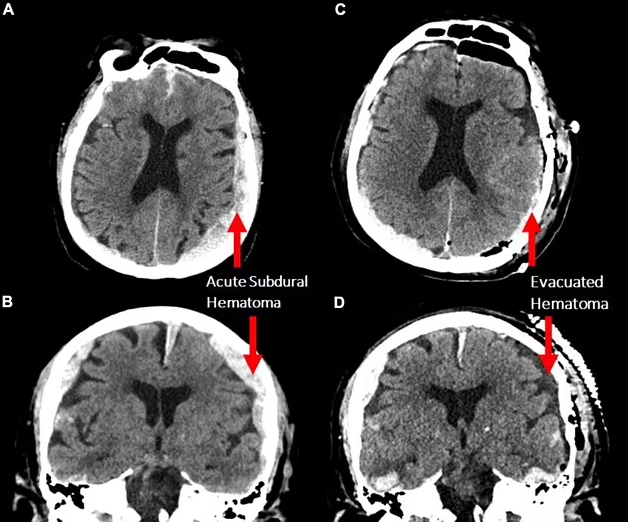

한 사례는 심장마비로 사망한 87세 남성이 뇌파 측정을 받던 도중 발생한 사건에서 비롯됐다. 당시 연구진은 그 환자의 뇌에서 ‘감마파(Gamma wave)’라고 불리는 고주파 신호가 분명히 관측됐다고 밝혔다.